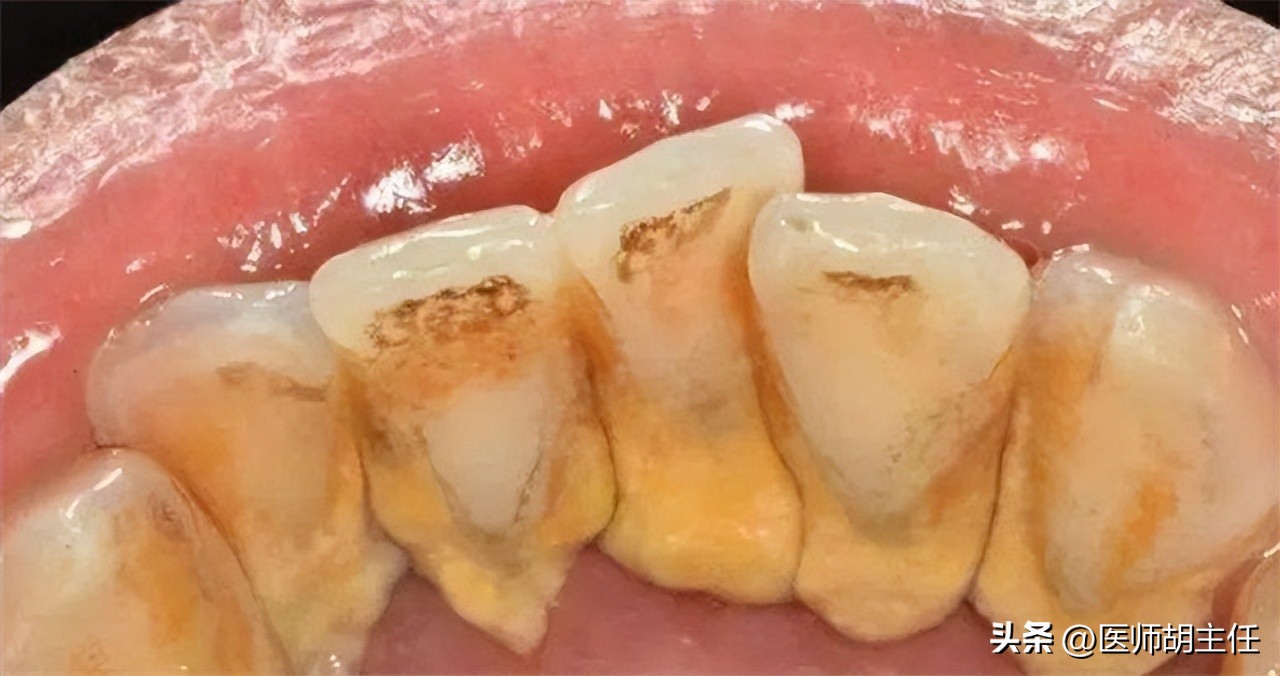

现在赵先生已经开始担忧起来,生怕是什么其他的疾病,于是赵先生前往我院口腔科进行诊治,待赵先生一张开嘴巴, 医生戴着口罩也闻到了一阵阵臭味传出来, 仔细一番检查,发现赵先生舌面、唇面和两侧结石都有很厚的牙石,诊断为 牙周炎、重度牙结石和牙龈萎缩 。

轻度就是整个口腔只有一点点牙石,需要去寻找;中度就是口腔有牙结石,但没有超过附近牙齿的三分之一;重度就是在中度的基础上,超过了附近牙齿的三分之一; 像赵先生这种,已经是达到重度了。

但是从没有牙结石发展到重度牙结石还是需要很长时间的,但是一旦像赵先生这样,过度吸烟、饮酒很容易使牙结石的形成速度加快。那吸烟和饮酒为什么会加快牙结石的形成呢,牙结石是怎么形成的呢?往下看下去吧!